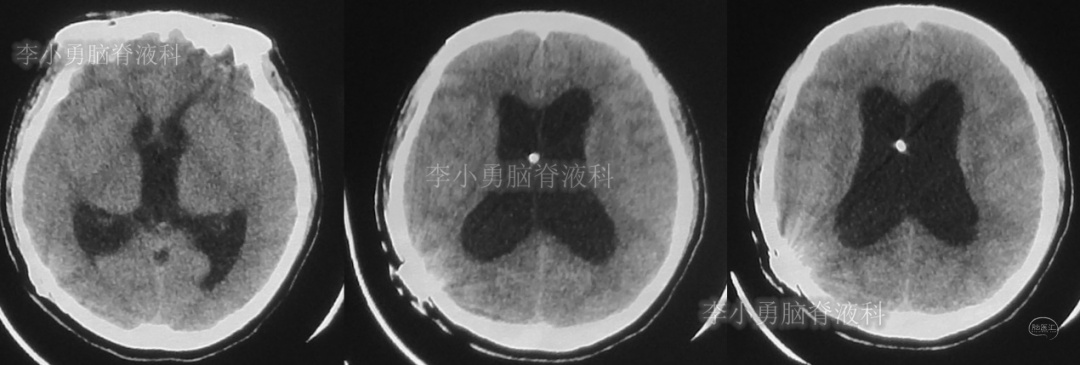

患者于2018年1月29日,突发头痛、头晕、恶心、呕吐,并高热40度。在当地医院门诊输入4天抗生素后发热缓解,但出现了双眼不能上视(眼球不能向上看)。5天后即2018年2月3日,在当地的第1家医院:浙江省海宁市某医院行头颅CT(图-1)发现脑室扩张,当地医院诊断为“梗阻性脑积水”。

图-1:2018年2月3日头颅CT